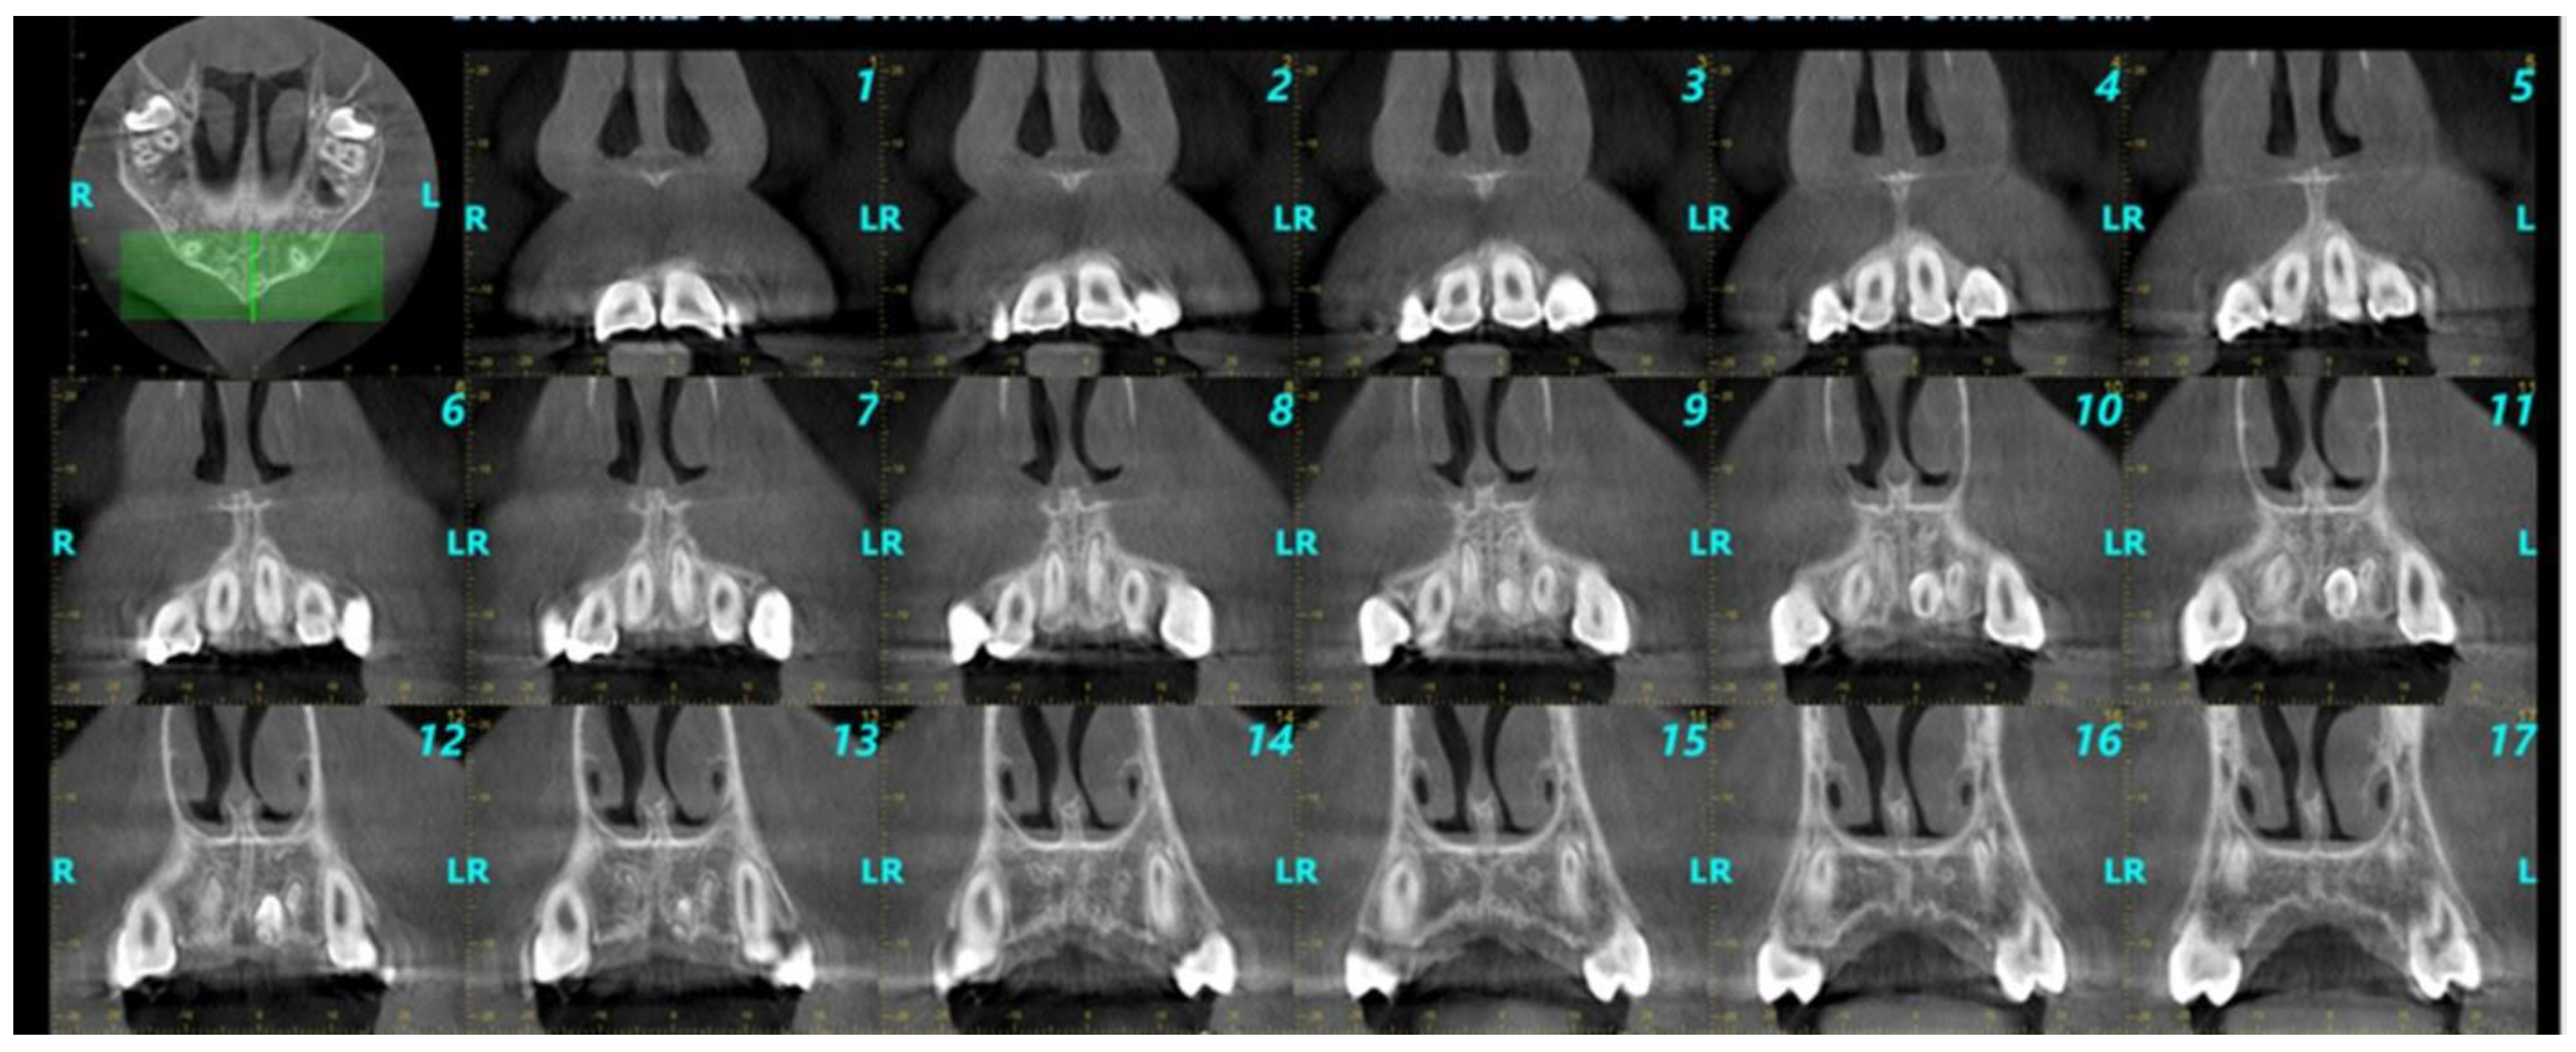

2.5. CBCT Scans’ Evaluation, Data Collection, and Extraction

- Number, size, shape, and location of the supernumerary teeth detected in the maxillary anterior area.

- Level of impaction of each supernumerary tooth (impacted, semi-impacted, fully erupted).

- Spatial orientation of supernumerary teeth in the sagittal plane.

- Relationship and proximity of supernumerary teeth to adjacent anatomical structures and adjacent teeth.

- Implications of supernumerary teeth on the dental arch.